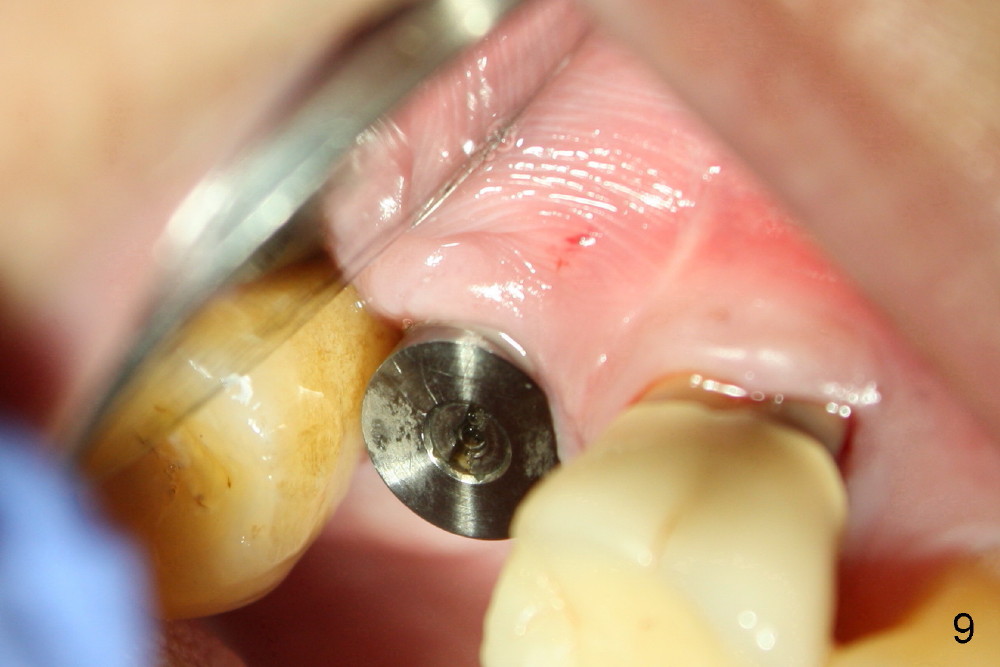

The implant threads (T) are exposed buccally. A flap is raised (Fig.5) with periosteum underscored. After placement of Osteogen (HA 300-500 µm) and Collaform (a collagen membrane, Fig.6*), the flap is sutured. There is no intra- or post-op nasal hemorrhage. The wound heals (Fig.7 (5 days postop), 8 (18 days)). It is apparent that the membrane (Fig.7 *) is replaced by the healing gingiva (Fig.8 *). Three months postop, the buccal gingiva looks normal (Fig.9) around the stable implant (Fig.10).